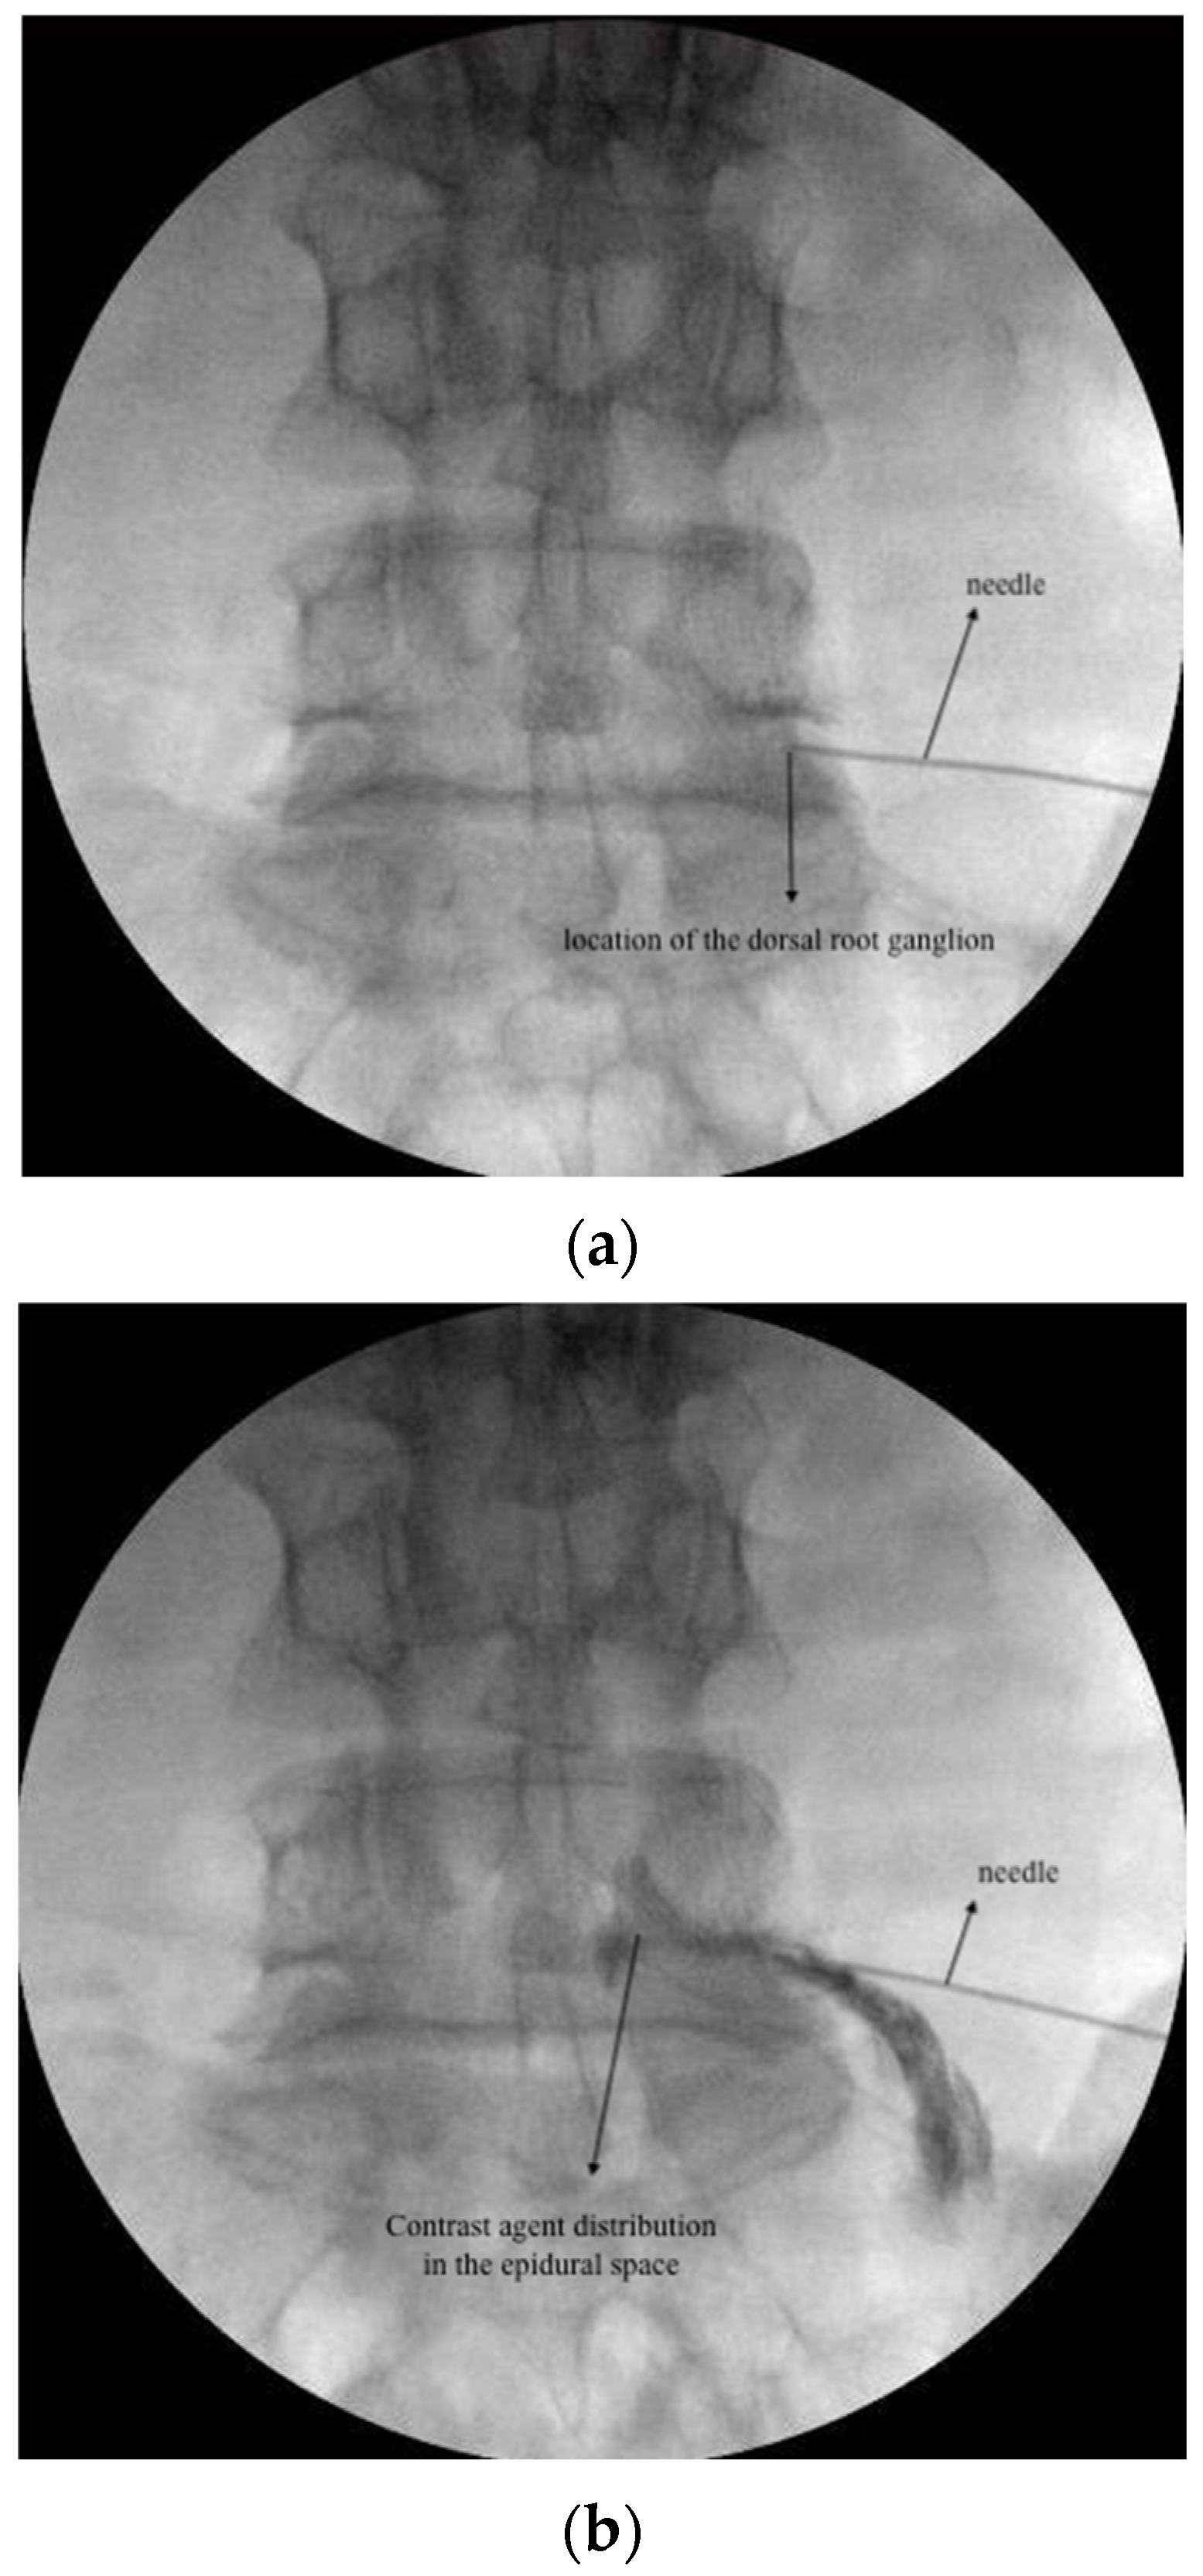

2.3.1. DRG PRF and TESI

2.3.2. CESI